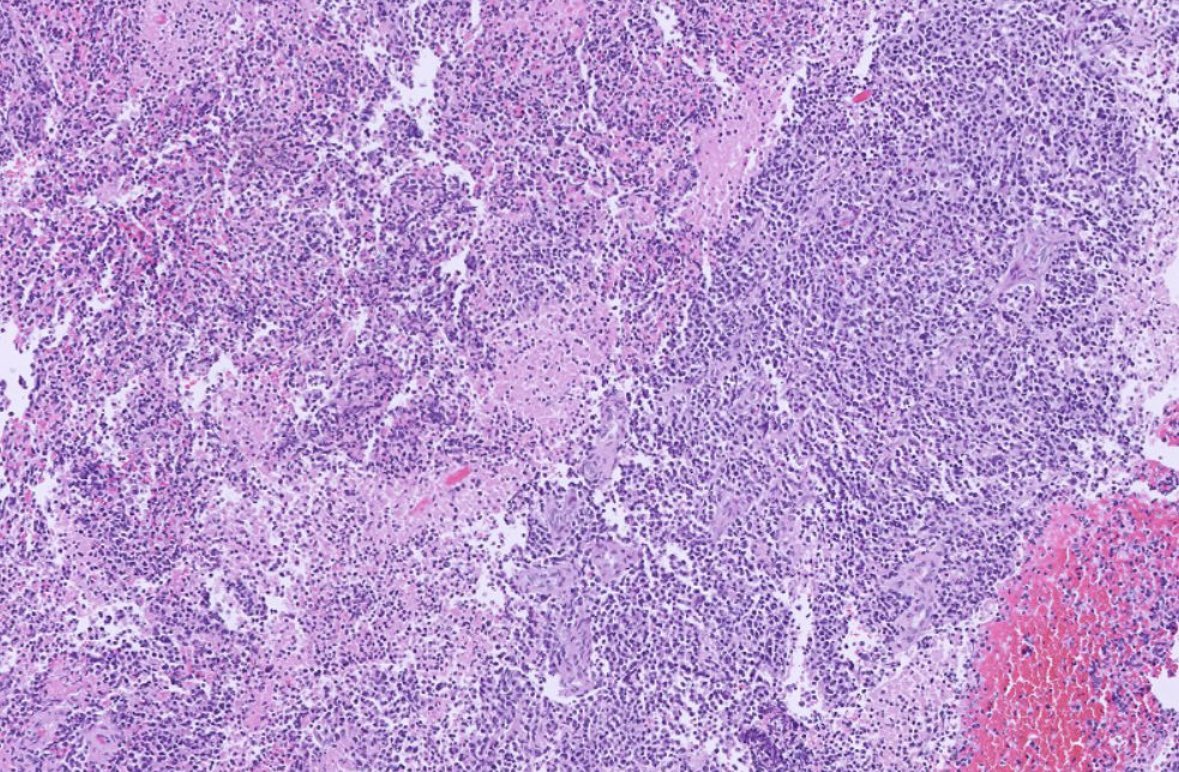

Adult Male. Dura based lesion. #PathX #PathTwitter #PathClassic #BSTPath #NeuroPath

3

22

55